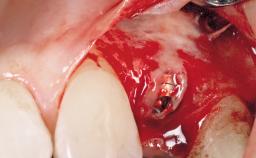

Type of Implants One-Piece

Placement Protocol Immediate implant placement

Socket Morphology Single-root socket

Socket Integrity Sufficient, with intact bone walls